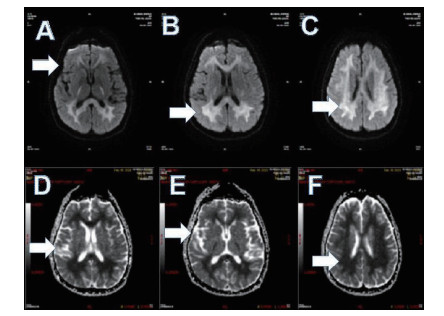

磁共振提示胼胝体局灶病变多为轻症患者(图 3);磁共振提示胼胝体双侧放射冠部散在病变多为中型患者(图 4);磁共振提示胼胝体双侧放射冠区弥漫性病变多为重症患者(图 5,6)。

| 图 3 ABCD为同例患者,病变为胼胝体局灶病变(箭头所示);EFGH为同例患者,病变为胼胝体右侧放射冠区局灶病变(箭头所示) |

| 图 4 此图为中型患者,可见胼胝体双侧放射冠部散在病变 |